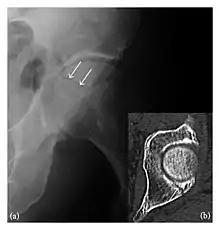

High-energy trauma fractures

Occult osseous injuries may result from a direct blow to the bone by compressive forces of adjacent bones against one another or by traction forces during an avulsion injury. Lesions in the tibial plateau, hip, ankle, and wrist are often missed. In a tibial plateau fracture, any disruption of the posterior and anterior cortical rims of the plateau should be sought. Impaction of subchondral bone will appear as an increased sclerosis of the subchondral bone (Figure 1). In the hip, posterior acetabular fractures also present subtle radiographic findings. The acetabular lines should then be carefully examined keeping in mind that the posterior rim, which is harder to see on X-rays, is more frequently fractured than the anterior rim (Figure 2). In the wrist, detection of carpal bone fractures is often challenging, with up to 18% of scaphoid fractures radiographically occult. Carpal fractures, especially the scaphoid, are associated with the risk of avascular necrosis. In apparently normal wrist radiographs from symptomatic patients, if there is history of a fall on an outstretched hand with pain in the anatomic snuffbox, suggesting scaphoid injury, the initial examination with posteroanterior, lateral, and pronation oblique views must be complemented by other specific views such as supination oblique and the "scaphoid" view A careful examination of cortices for evidence of discontinuity or offset and cancellous bone for lucency is necessary (Figure 3).[1]

a

b

c

Figure 3: A 26-year-old man presenting with wrist pain after being assaulted. (a) Initial anteroposterior radiograph shows a subtle linear lucency within the scaphoid extending to the scaphocapitate articular surface that was overlooked (arrow). (b) Initial "scaphoid" view was negative. (c) Followup anteroposterior radiographs, 12 days later, shows obvious scaphoid fracture (arrows).[1]